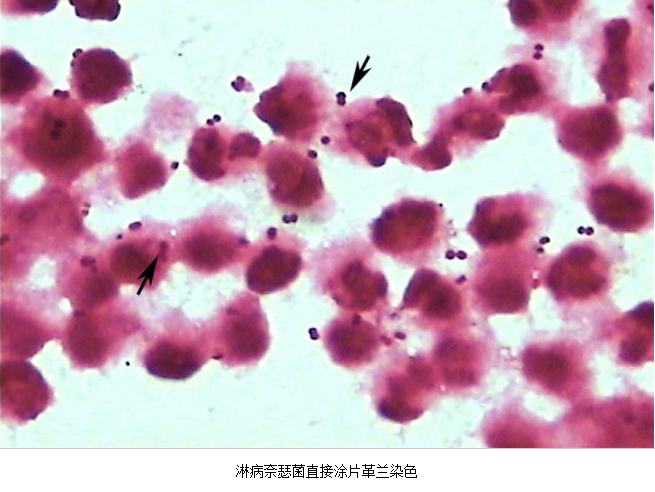

(1)子宫颈管脓性分泌物涂片作革兰染色,中性粒细胞>30/高倍视野。

急性子宫颈炎患者,子宫颈管脓性分泌物涂片作革兰氏染色,中性粒细胞>30/高倍视野,

箭头处为中性粒细胞内可见革兰氏阴性双球菌

3.病原体检测 应作衣原体及淋病奈瑟菌的检测,以及有无细菌性阴道病及滴虫阴道炎。检测淋病奈瑟菌常用的方法有:①分泌物涂片革兰染色,查找中性粒细胞内有无革兰阴性双球菌,由于子宫颈分泌物的敏感性、特异性差,不推荐用于女性淋病的诊断方法。②淋病奈瑟菌培养,为诊断淋病的金标准方法。③核酸检测,包括核酸杂交及核酸扩增,尤其核酸扩增方法诊断淋病奈瑟菌感染的敏感性及特异性高。检测沙眼衣原体常用的方法有:①衣原体培养,因其方法复杂,临床少用。②酶联免疫吸附试验检测沙眼衣原体抗原,为临床常用的方法。③核酸检测,包括核酸杂交及核酸扩增,尤以后者为检测衣原体感染敏感、特异的方法。但应做好质量控制,避免污染。